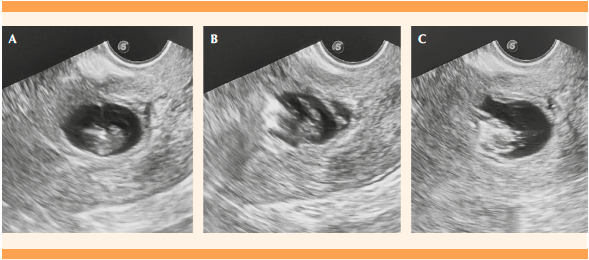

La técnica consistió en la administración de anestesia raquídea (Figura 1) y revisión ecográfica transvaginal para valorar y confirmar las características ecográficas de embarazo en la cicatriz de cesárea (Figura 2). Enseguida, se ajustó al transductor una aguja Spinocan - 20 y se procedió a la punción intravaginal, de forma eco guiada, a la altura del fórnix cervical anterior. Al ingresar al saco gestacional (Figura 3) se aspiró su contenido (2 cc). Cuando hubo embriocardia se administró cloruro de potasio (KCl) (2 cc = 2mEq/mL) para producir la asistolia del embrión. Posteriormente se administró una dosis única intrasacular de metotrexato (25 mg) (Figura 4). Se volvieron a revisar los hallazgos ecográficos (Figura 5) y se retiró el transductor vaginal. Al terminar el procedimiento se verificó la hemostasia en la cavidad vaginal. Para el seguimiento de las concentraciones de la β-hCG se efectuó un control a las 48 horas posteriores al procedimiento, que se tomó como línea de base. Las tomas posteriores de β-hCG se repitieron cada semana hasta su negativización que dio pie a considerar al tratamiento exitoso. Se dieron instrucciones para acudir de inmediato a consulta en caso de sangrado vaginal, fiebre, o cualquier otro síntoma relacionado con el tratamiento. Éste se consideró fallido cuando las concentraciones de la β-hCG se reportaron en meseta o en aumento.

Fuente: Archivo del estudio.

Figura 5 (A) Inyección intrasacular de metotrexato. Se evidencia la aguja hiperecogénica intrasacular. (B) Se aprecia cómo entra líquido a la cavidad del saco gestacional donde llena y deteriora la imagen embrionaria. (C) Imagen ecográfica final, donde no se distingue un embrión claro, lleno del medicamento previamente inyectado.